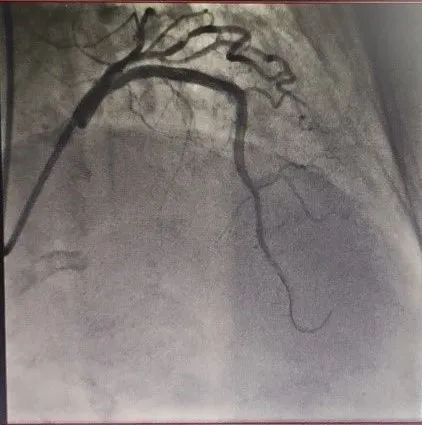

CAG显示LAD近中段闭塞

患者为60岁的老年男性,因反复的心绞痛在当地医院进行治疗,冠状动脉造影发现左前降支中段闭塞并伴有严重钙化,当地医院进行反复尝试,虽然导丝可通过闭塞病变到达远端,但是因钙化严重球囊无法通过,无法进一步治疗。

为解决问题,患者辗转于多家医院,均告知很难开通,必须搭桥。之后患者慕名找到刘巍主任。刘巍主任阅片后发现,病变不仅在前降支中段,对角支也有严重狭窄,考虑如果使用旋磨并不能保护对角支血流,所以决定使用准分子激光技术消融斑块开通血管。手术过程非常艰难,由于前降支血管闭塞,之前外院的医生已经对血管进行扩张处理,所以导丝很容易进入到血管夹层中,反复尝试才将导丝经过真腔送至血管远端。使用球囊扩张后,计划使用IVUS检查对前降支进行评估,但由于钙化严重IVUS无法通过,如果勉强植入支架,支架肯定膨胀不良,后果不堪设想。

刘巍主任团队应用0.9mmECLA激光导管多病变处反复进行高能量消蚀,松解钙化病变,之后成功植入支架,术后效果非常满意。